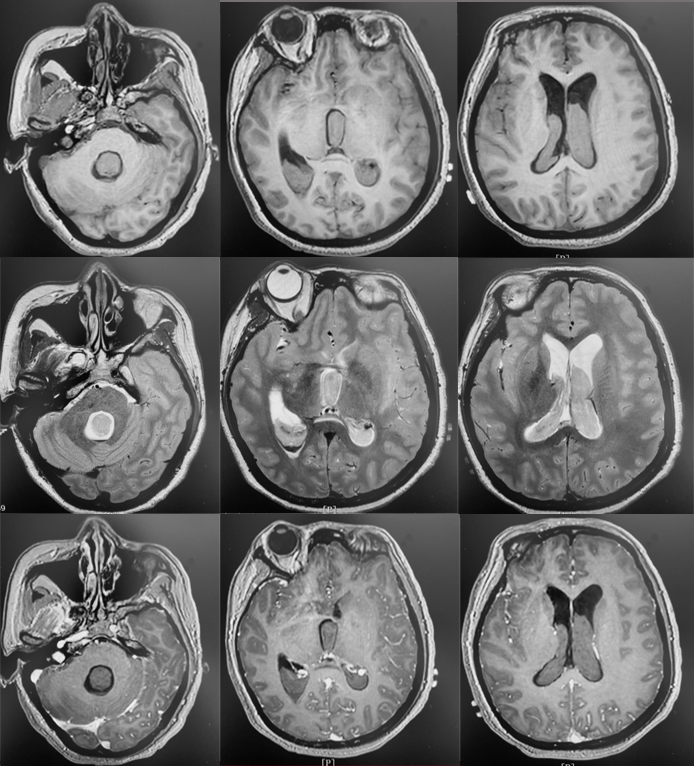

术前诊断

烟雾病

脉络膜前动脉假性动脉瘤

脑室旁动脉瘤较为罕见,文献中报告的病例不到60例,其中19例与烟雾病有关。大多数脑室旁动脉瘤继发于恶性高血压、感染或血管畸形,也有部分脑室旁动脉瘤是特发性的[1]。

有观点认为此类动脉瘤可以保守治疗,因为较小的脑室旁动脉瘤可能自发消退,但同样存在保守治疗的病例预后不佳[1-4]。深部动脉瘤通过血管内介入治疗往往能取得较好的疗效,治疗能否成功关键取决于载瘤动脉直径[5]。血管内栓塞通常是烟雾病患者脑室旁动脉瘤的首选方案,因为可以避免开颅手术对脑实质的损伤及相关的缺血事件发生[1]。在一项病例系列研究[6]中,血管内栓塞成功治疗了7例(88%)烟雾病伴脑室旁动脉瘤且无围术期并发症,其中6名患者在出院时完全康复(75%)。然而,烟雾病患者载瘤动脉往往十分迂曲,且动脉瘤容易破裂[5]因此血管内治疗往往充满挑战。显微手术夹闭是动脉瘤的传统治疗方法,但在治疗深部动脉瘤时,术中破裂的风险可能更高。微创手术如小骨窗和神经内镜已用于治疗颅内深部病变,并取得了不同程度的成功。